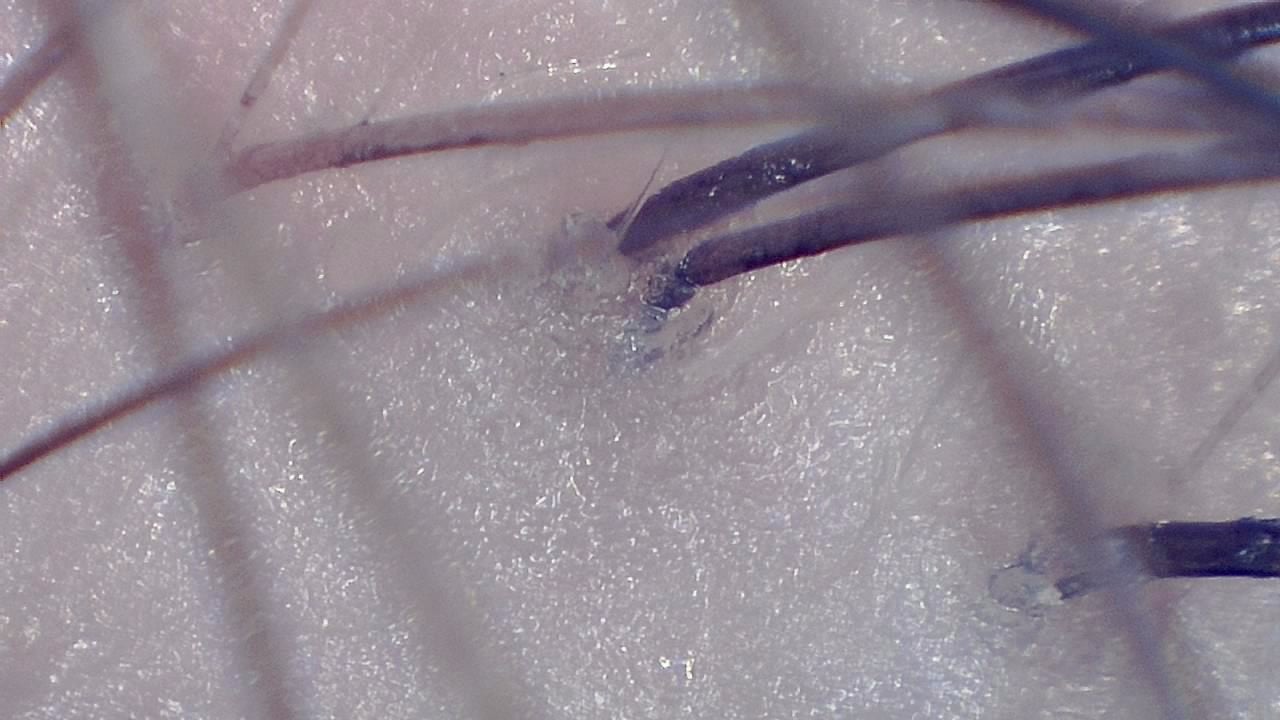

Portable magnified viewing for scalp surface, hair shafts, follicular openings, and visual documentation over time.

Trichoscopy is a non-invasive visual examination technique used by trained professionals to observe the scalp surface and hair shafts. Smart G-Scope provides a portable USB workflow for magnified viewing and image capture.

The device can support documentation of hair shaft appearance, scalp surface features, follicular openings, and visible changes over time. It is most useful when images are captured under consistent lighting and positioning.

What you can observe

- Hair shafts and visible shaft diameter variation.

- Scalp surface texture and visible follicular openings.

- Magnified viewing of hair shafts, scalp surface, and visible follicular openings.